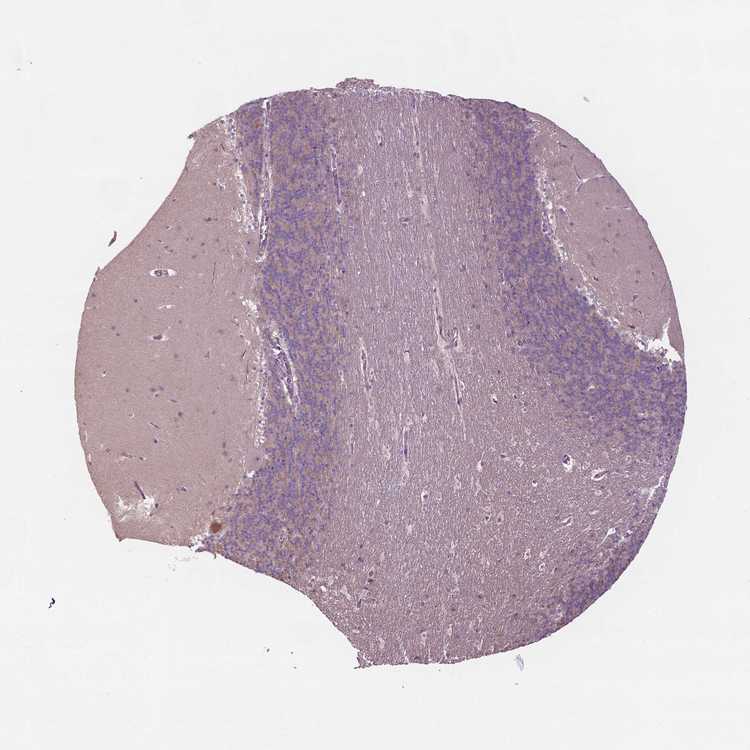

BRAIN CEREBELLUM Show tissue menu

CEREBELLUM - Expression summary

CEREBELLUM - Antibody stainingi

Antibody staining in the annotated cell types in the current human tissue is reported as not detected, low, medium, or high, based on conventional immunohistochemistry profiling in selected tissues. This score is based on the combination of the staining intensity and fraction of stained cells.

Each image is clickable and will lead to virtual microscopy that enables deeper exploration of all samples and also displays staining intensity scores, fraction scores and subcellular localization as well as patient and tissue information for each sample.

Antibody HPA012636

Purkinje cells Low

Cells in granular layer Low

Cells in molecular layer Not detected